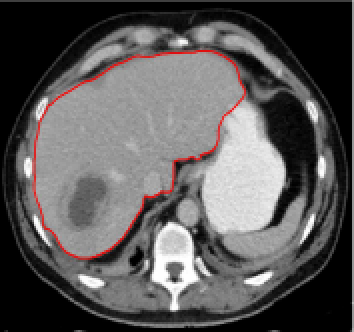

Four sets of test results are shown below. In Test 1 we compare models M1 – M6 to the proposed model M7 for two images which are hard to segment. The first is a CT scan from which we would like to segment the lower portion of the heart, the second is an MRI scan of a knee and we would like to segment the top of the Tibia. See Figure 9 for the test images and the marker sets used in the experiments. In Test 2 we will review the sensitivity of the proposed model to the main parameters. In Test 3 we will give several results achieved by the model using marker and anti-marker sets. In Test 4 we show the initialisation independence and marker independence of the Geodesic Model on real images.

Refer to captionRefer to captionRefer to captionRefer to caption

(i)                                 (ii)                                 (iii)                                 (iv)

Figure 9: Test 1 setting: (i) Image 1;  (ii) Image 1 with marker and anti-marker set shown in green and pink respectively;  (iii) Test Image 2; (iv) Image 2 with marker set shown.

In this test we give the segmentation results for models M1 – M7 for the two challenging test images shown in Figure 9. The marker and anti-marker sets used in the experiments are also shown in this figure. After extensive parameter tuning, the best final segmentation results for each of the models are shown in Figures 10 and 11. For M1 – M4 we obtain incorrect segmentations in both cases. In particular, the results of M2 and M4 are interesting as the former gives poor results for both images, and the latter gives a reasonable result for Test Image 1 and a poor result for Test Image 2. In the case of M2, the regularisation term includes the edge detector and the distance penalty term (see (4)). It is precisely this which permits the poor result in Figures 10(b) and 11(b) as the edge detector is zero along the contour and the fitting terms are satisfied there (both intensity and area constraints) – the distance term is not large enough to counteract the effect of these. In the case of M4, the distance term and edge detector are separated from the regulariser and are used to weight the Chan-Vese fitting terms (see (9)). The poor segmentation in Figure 11(b) is due to the Chan-Vese terms encouraging segmentation of bright objects (in this case), weighting ω𝜔\omega enforces these terms at all edges in the image and near \mathcal{M}. In experiments, we find that M4 performs well when the object to segment is of approximately the highest or lowest intensity in the image, however when this is not the case, results tend to be poor. We see that, in both cases, models M5 and M6 give much improved results to M2 and M4 (obtained by incorporating the geodesic distance penalty into each). The proposed Geodesic Model M7 gives an accurate segmentation in both cases. It remains to compare M5, M6 and M7. We see that M5 is a non-convex model (and cannot be made convex [39]), therefore results are initialisation dependent. It also requires one more parameter than M6 and M7, and an accurate set \mathcal{M} to give a reasonable area constraint in (4). These limitations lead us to conclude M6 and M7 are better choices than M5. In the case of M6, it has the same number of parameters as M7 and gives good results. M6 can be viewed as the model M7 with weighted intensity fitting terms (compare (18) and (30)). Experimentally, we find that the same quality of segmentation result can be achieved with both models generally, however M6 is more parameter sensitive than M7. This can be seen in the parameter map in Figure 12 with M7 giving an accurate result for a wider range of parameters than M6. To show the improvement of M7 over previous models, we also give an image in Figure 13 which can be accurately segmented with M7 but the correct result is never achieved with M6 (or M3). Therefore we find that M7 outperforms all other models tested M1 – M6.